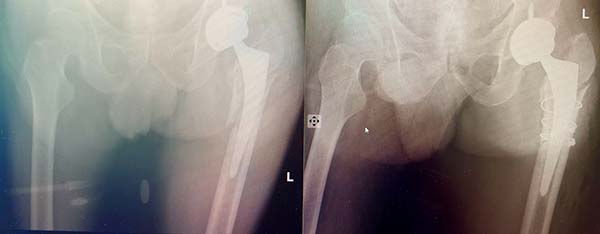

随后,在麻醉科与手术室团队的密切配合下,骨科张轶超主任、沈松坡主任主刀,为患者开展假体周围骨折切开复位内固定术。为应对术中可能出现的各类突发状况,团队提前备齐备足翻修型假体、取出器械及多种固定材料。术中,专家团队根据实际伤情,精准采用金属与非金属捆扎带完成骨折复位固定。整个手术过程有条不紊,患者生命体征始终保持平稳。

图为患者术前术后X光片,骨折复位满意